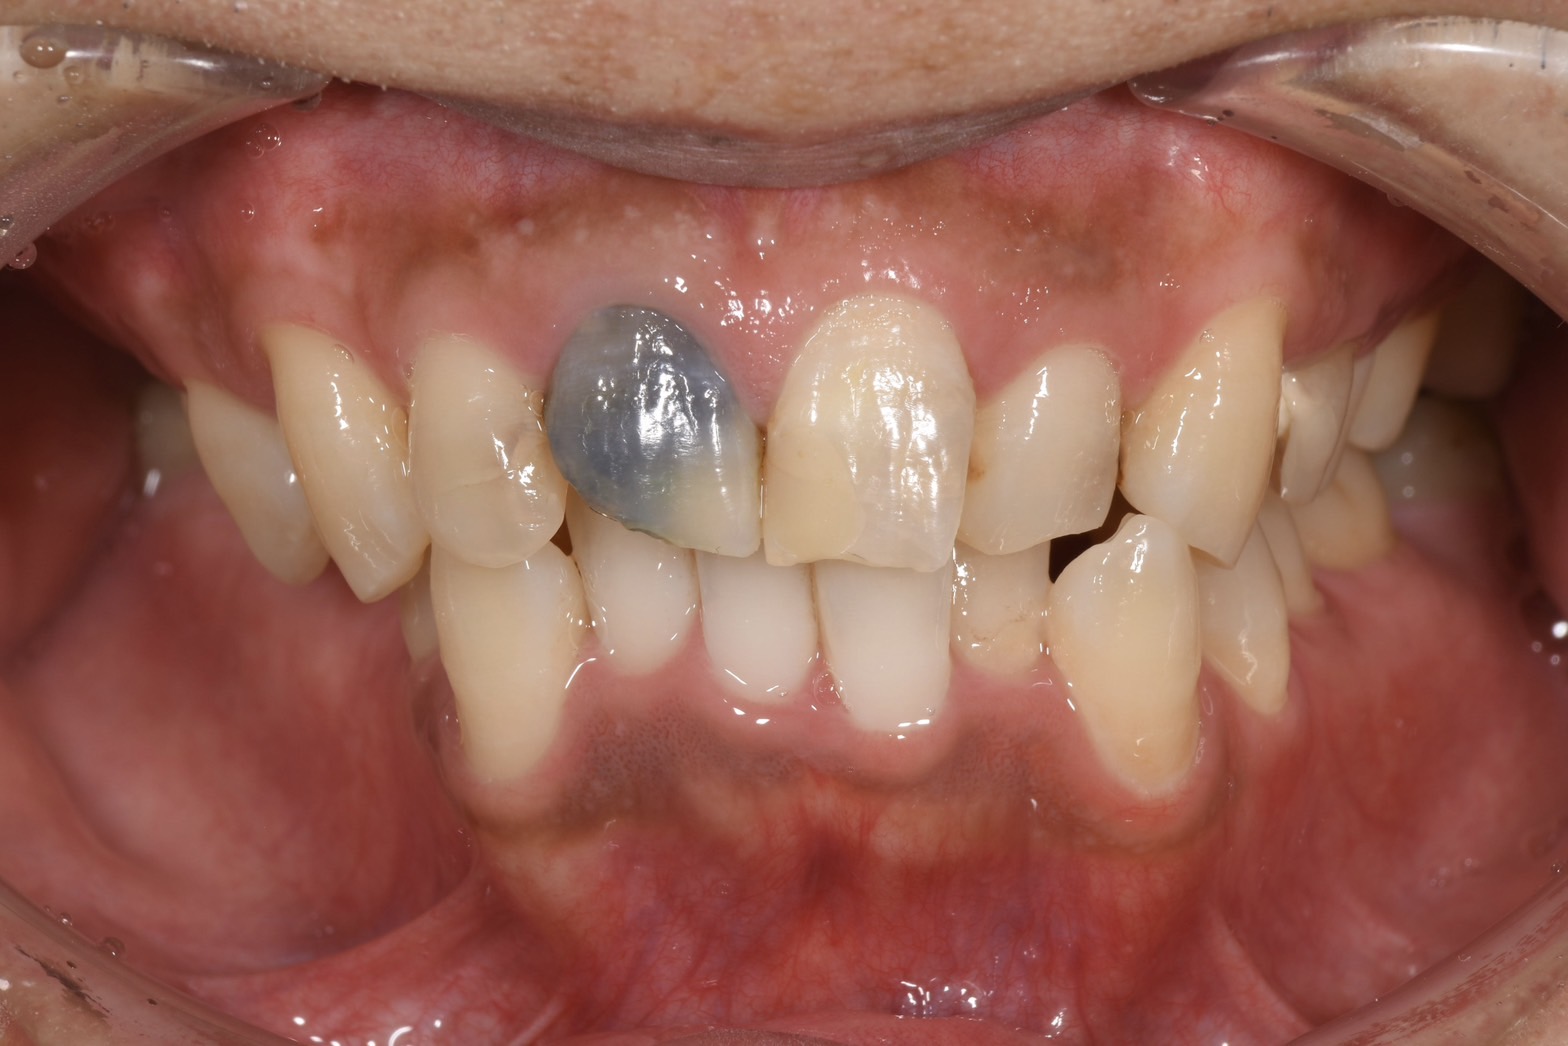

①は一度装着してしまうと入れ墨のように歯や歯肉に金属色が染み込んでしまい、被せ物をセラミックにしても完全に綺麗に治療することが難しくなります。

この写真では被せ物は元々されていませんが、土台に金属を使用されてたため、金属色が歯と歯茎に染み込んでしまっていました。

真ん中から見て右側の歯は大きな虫歯があったため根管治療後、左側と2本同時にセラミックで治療しましたが、メタルが使われていないため綺麗に仕上がっています。